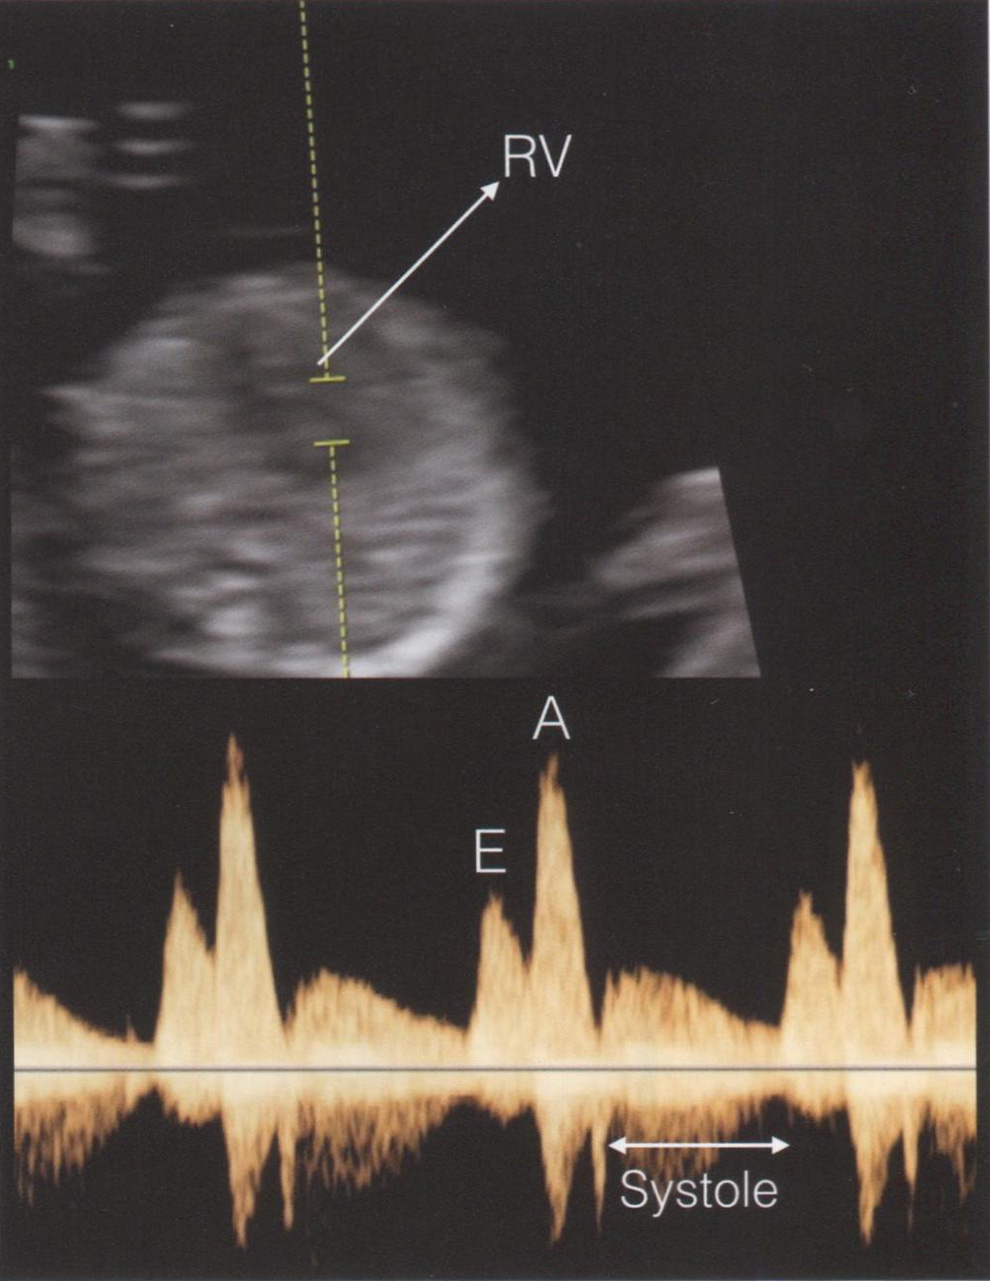

Рис. 1.5. Аксиальная плоскость сканирования грудной клетки плода в 13 нед беременности. Контрольный объем импульсноволнового допплера помещен на область клапана так, чтобы захватить как основной поток, так и регургитацию (при ее наличии). В данном случае в систолу (Systole, двунаправленная стрелка) регургитация отсутствует, кривая скорости кровотока нормальная: пик Е отражает раннюю диастолу, пик А - четвертый тон сердца. Критерии для оптимальной визуализации кривой скорости кровотока трикуспидального клапана приведены в табл. 1.4. RV - правый желудочек.

Трикуспидальная регургитация

Поток крови через трикуспидальный клапан можно оценить с помощью импульсноволновой допплерометрии и режима цветового допплеровского картирования (ЦДК) при сканировании четырехкамерного среза сердца, когда верхушка сердца ориентирована к датчику. Контрольный объем помещается на область фиброзного кольца клапана (рис. 1.5). В I триместре беременности трикуспидальная регургитация встречается у большинства плодов с анеуплоидиями (трисомии 21, 18, 13) и с грубыми пороками сердца. Небольшой регургитационный поток через створки клапанов в I триместре беременности является частой находкой и встречается у большинства здоровых плодов. В табл. 1.4 приведены основные критерии для определения трикуспидальной регургитации в режиме скрининга на анеуплоидии и пороки сердца. Трикуспидальная регургитация, соответствующая этим критериям, встречается только у 1% плодов с нормальным кариотипом, у 55% плодов с трисомией 21 и в 1/3 случаев у плодов с трисомиями 18 и 13. Также, как и в случае регистрации кровотока в венозном протоке, мы не рекомендуем проводить оценку трикуспидальной регургитации у всех плодов. Это исследование показано при высоком риске наличия у плода порока сердца и при среднем риске по анеуплоидиям.